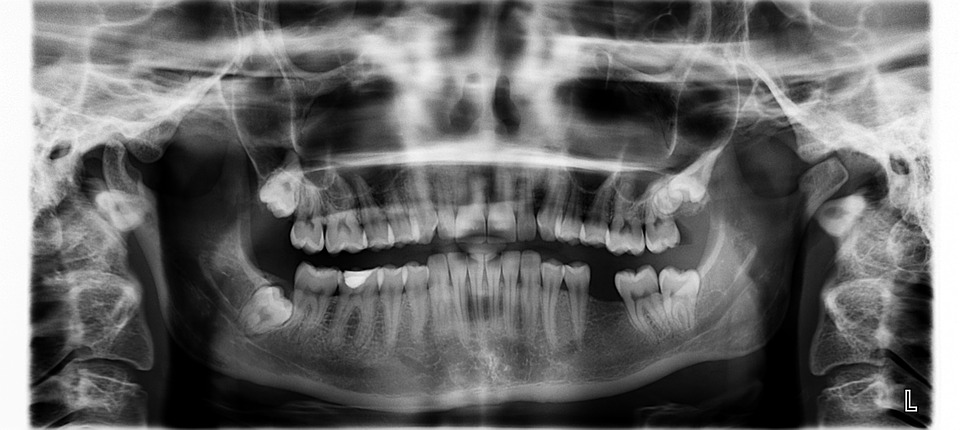

Traditionally, dentists assess the condition of their patients' gums using an instrument called periodontal probe, which is a thin, hook-like metal tool that has labels like a measuring stick and is placed in between the teeth and gums to see how much the gums have shrunk back from the teeth, causing the formation of pockets.

A pocket depth that measures one to two millimeters shows healthy gums while a pocket depth of three mm is indicative of gum disease. The deeper the pockets, the worse the gum disease. (Related: Contrary to what your dentist may tell you, you CAN reverse tooth decay, new research finds.)

This technique makes it possible for dentists to visualize a full map of the pocket depth around each tooth – a remarkable improvement over the traditional method.